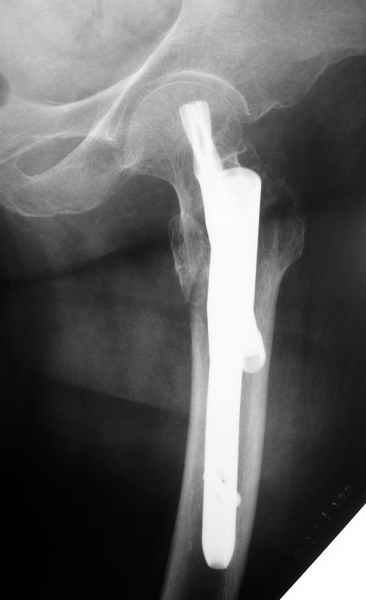

Как раз недавно у меня был примерный случай: больному 36 лет, поступил ночью, травма в результате мотоциклетной аварии, кроме чрезвертельного и спирального перелома левого бедра имеется переломы костей предплечья с этой же стороны. Скелетное вытяжение, а на следующий день больной про оперирован на ортопедическом столе с дистракцией. Чтобы не расколоть чрезвертельный перелом провели временную спицу ближе к переднему кортексу, из малого разреза костодержатель для репозиции, а фиксацию провели антиградным штифтом. Этапы операции на снимках.

Джолдас Кульджанов

Да, сейчас это и у нас самый напрашивающийся выбор. Сделали гвоздем ChM, картинки в приложении.

У молодых реконструкционный гвоздь самое то. При остеопорозе надо что-то помассивнее.